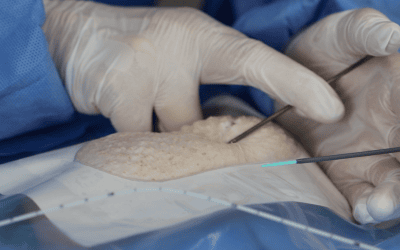

Actualmente, los reservorios, los catéteres Hickman, los PICCs, los catéteres centrales, los midlines y los catéteres cortos pueden venir con la característica “compatible con la alta presión” (llamada también CT rated o Power Injectable). Sin embargo, es fundamental comprobar siempre que nivel de alta presión y de alto flujo permiten para asegurarse que sean adecuados para la prueba que se quiera llevar a cabo.